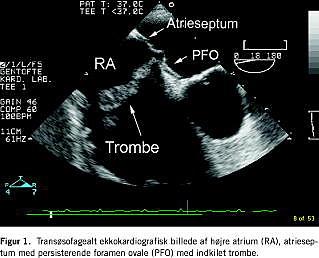

Vi rapporterer om et tilfælde af lungeemboli (LE), hvor man ved transtorakal og transøsofageal ekkokardiografi påviste en intrakardiel trombe i højre atrium fastsiddende i et persisterende foramen ovale (PFO).

Efter perfusionsskintigrafi forstærkedes mistanken om lungeemboli, og ved transtorakal ekkokardiografi (TTE) verificeredes en trombe i højre atrium. Der var dilatation af højre ventrikel og et øget systolisk pulmonaltryk på 60 mmHg. Ved transøsofageal ekkokardiografi (TEE) fandtes tromben at være indkilet i et PFO (Figur 1 ), men uden at penetrere til venstre atrium. Der var ingen tromber i v. cava eller aa. pulmonales.